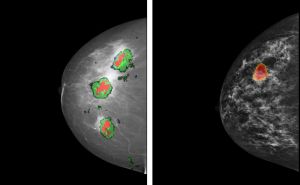

Dr. Torsten Hopp, Postdoktorand am Institut für Prozessdatenverarbeitung und Elektronik (IPE) des KIT, bekommt den zweiten Preis für seine am IPE angefertigte Doktorarbeit „Kombination von Röntgenmammographie und 3D-Bildgebung für die Brustkrebsdiagnose“. Bei Brustkrebs hängt die Überlebenswahrscheinlichkeit stark vom Zeitpunkt ab, zu dem der Tumor erkannt wird. Das Standardverfahren in der Brustbildgebung ist derzeit die Röntgenmammographie. Um eine genauere Diagnose zu stellen, werden darüber hinaus verschiedene bildgebende Verfahren, wie die Magnetresonanztomographie (MRT), mit der Röntgenmammographie kombiniert. Der Vergleich der unter unterschiedlichen Bedingungen aufgenommenen Bilder ist allerdings schwierig. Torsten Hopp hat ein automatisches Bildregistrierungs-Verfahren entwickelt, das es ermöglicht, zweidimensionale Mammogramme mit dreidimensionalen Bildern ergänzender Verfahren, wie MRT oder Ultraschall-Computertomographie (USCT), direkt zu vergleichen: Anhand eines Computermodells wird die Kompression der Brust während der Mammographie simuliert. Anschließend wird die räumliche Beziehung der Bilder durch intuitive Werkzeuge dargestellt, beispielsweise durch Bildfusion, das heißt Kombination von Informationen zweier Verfahren in einem Bild. Die Software wurde mit einer großen Zahl klinischer Datensätze getestet und für den Einsatz in einer Klinik vorbereitet.

Bildfusion: Verdächtige Struktur aus MRT-Ergebnis (links) oder USCT-Ergebnis (rechts) wird dem Röntgenmammogramm überlagert (Abb.: Torsten Hopp, KIT)